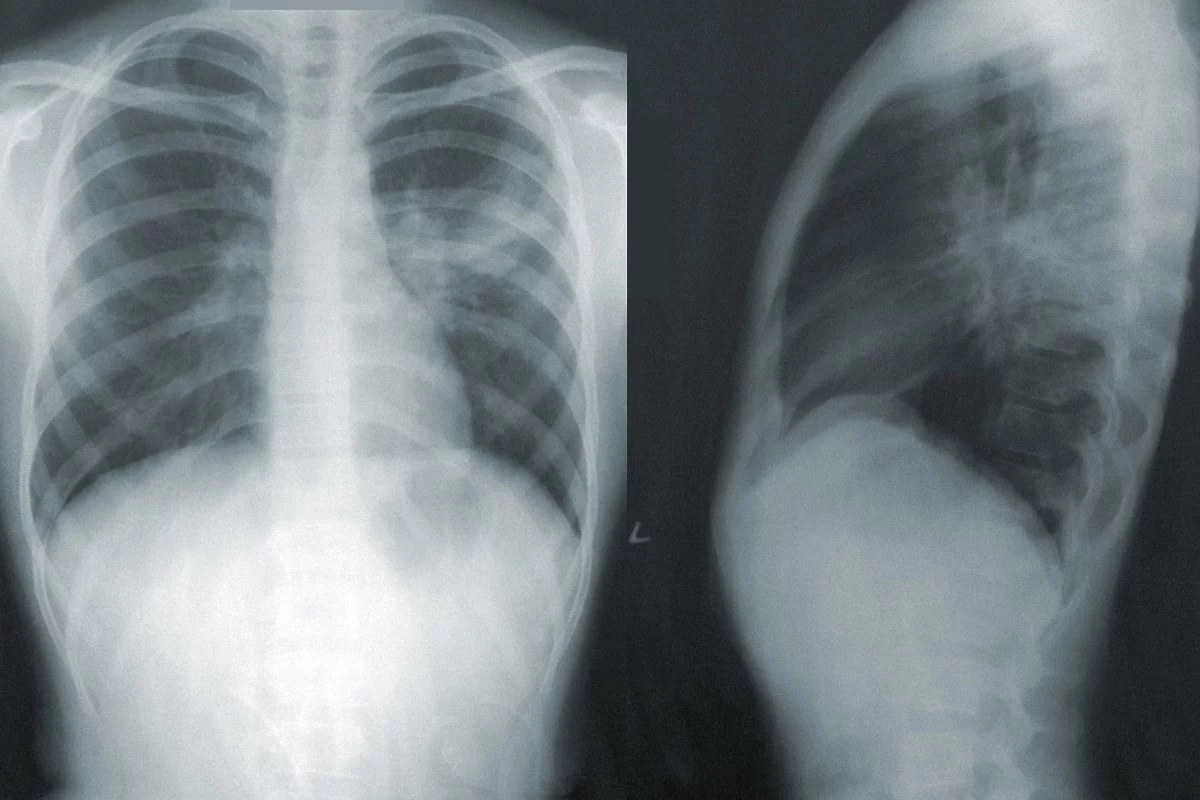

“most types of pneumonia will show up on imaging scans as white patches in the lungs, indicating areas of inflammation.